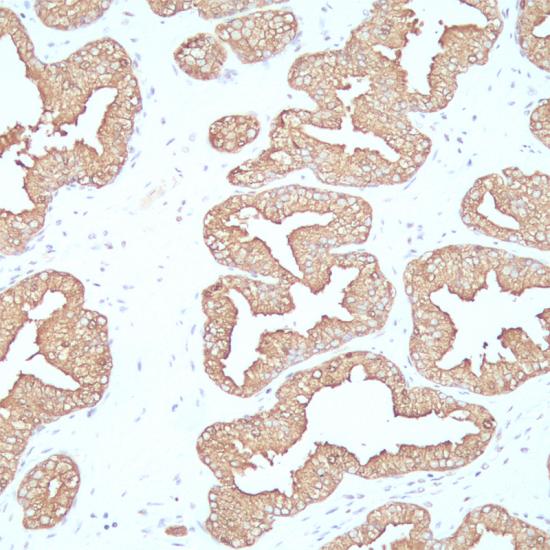

PSAP(前列腺特異性酸性磷酸酶)是由前列腺上皮細(xì)胞分泌的一種酸性磷酸酶的同工酶,在正常前列腺、增生的前列腺組織和前列腺癌中均表達(dá)PSAP。此抗體主要用于前列腺癌和轉(zhuǎn)移性前列腺癌的診斷。

PSAP抗體試劑(免疫組織化學(xué)) 閩廈械備20180111號

• 陽性部位:

細(xì)胞漿

• 陽性對照:

前列腺癌